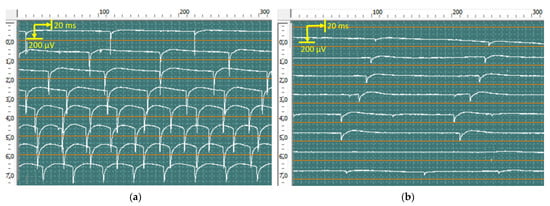

2.5. Electrophysiology

2.5.1. Evoked Electromyography

2.5.2. Quantitative Needle Electromyography